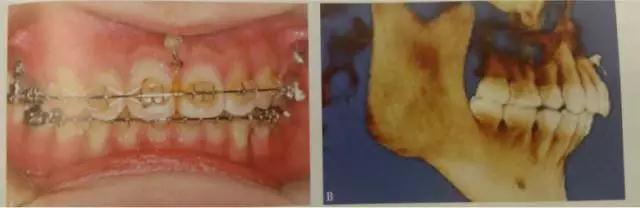

這是臨床上常見的應(yīng)用方式,多用于需要強(qiáng)支抗內(nèi)收前牙,常種植于第二前磨牙與第一磨牙、第一磨牙與第二磨牙之間,應(yīng)根據(jù)X線片觀察牙根間距離和鄰近解剖結(jié)構(gòu)確定具體部位,采用微種植體一方面可以獲得支抗以盡可能內(nèi)收前牙,另一方面可整體內(nèi)收6個前牙而不擔(dān)心支抗問題,節(jié)省了調(diào)節(jié)時間。